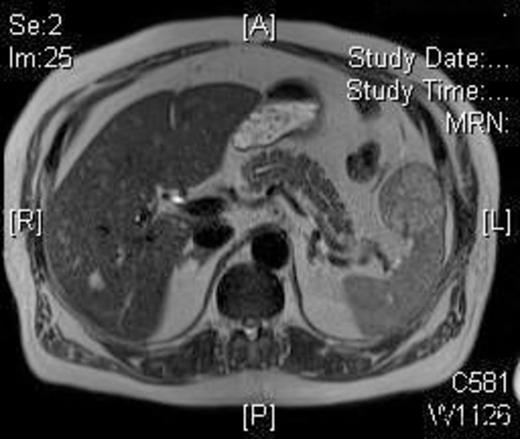

A 58-year-old Caucasian man presented with chest pain, on a background of type-II diabetes mellitus, hypertension and hypercholesterolaemia. A Cardiologist excluded ischaemic heart disease. Full blood count was normal, and an ultrasound scan of the abdomen revealed a 5.5-cm splenic lesion. Computed tomography (CT) revealed a 55mm X 36mm hypodense lesion in the upper pole of the spleen, while magnetic resonance imaging (MRI) demonstrated a well-circumscribed exophytic round mass arising from the anterior aspect of the spleen with features compatible with a benign solid tumour of uncertain malignant potential and multiple liver haemangiomas [Figures 1 and 2]. We proceeded to LPS after the patient had received preoperative vaccinations lest total splenectomy might be necessary.

T2W weighted image demonstrating a well circumscribed, round mass arising exophytically from the anterior aspect of the spleen with an intermediate T2W signal intensity.